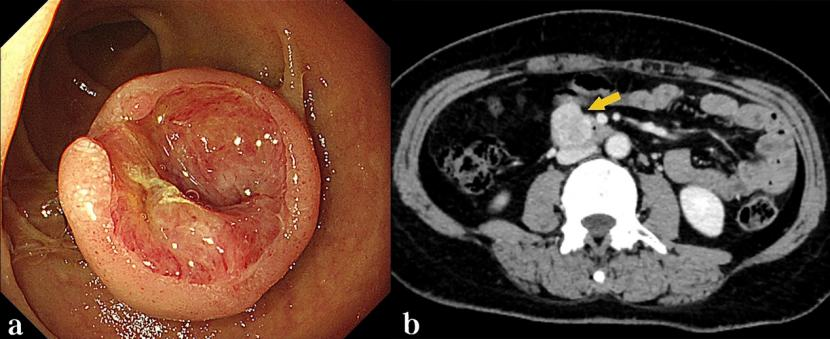

图片

患者女性,47岁,因“黑便”于2023年11月就诊。胃镜检查提示十二指肠存在一直径约2 cm的黏膜下病变,表面伴溃疡,活检病理结果提示为胃肠道间质瘤(图1a),腹部增强CT考虑胃肠道间质瘤(图1b),未见周围脏器侵犯及淋巴结转移表现。经多学科团队评估,并与患者充分沟通内镜与外科手术的利弊后,患者最终选择内镜下切除肿瘤。胡兵团队决定行EFTR手术切除肿瘤(图2):首先进行黏膜下注射生理盐水(图2a),为肿瘤剥离创造操作空间;逐层剥离肿瘤(图2b),病灶已向肠腔外生长(图2c),实施全层切除直至肿瘤完整剥离(图2d),用圈套器取出肿瘤(图2e);采用双层荷包缝合技术,通过尼龙环联合钛夹封闭肠壁缺损(图2f);术毕行腹腔穿刺排气及鼻肠管胃肠减压。术后切除标本大小约4.0 cm×3.0 cm×2.0 cm,病理结果证实为胃肠道间质瘤(低危)且达到R0切除(图3)。术后6个月胃镜检查显示创面愈合良好(图4)。随访20个月,患者未出现内镜手术相关并发症、肿瘤复发或转移。

图1 术前十二指肠检查结果。1a.白光胃镜下显示十二指肠黏膜下病变,表面伴溃疡;1b.CT提示胃肠道间质瘤(黄箭)

图2 十二指肠间质瘤EFTR操作过程。2a.黏膜下注射生理盐水;2b.逐层分离肿瘤组织;2c.肿瘤向肠腔外生长;2d.持续全层切除直至肿瘤完整剥离;2e.用圈套器取出肿瘤标本;2f.双层荷包缝合封闭肠壁缺损